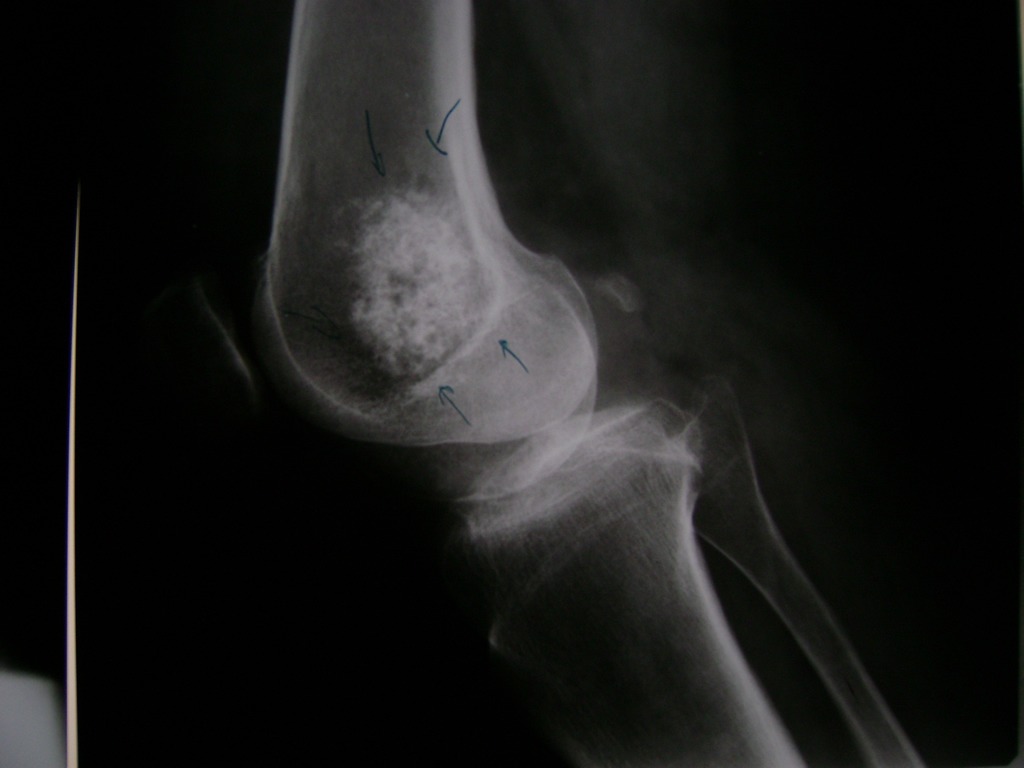

La artroscopia de rodilla es un cirugía en el cual la estructura interna de la articulación es examinada ya sea para realizar un diagnostico o para realizar un tratamiento, este procedimiento se realiza utilizando un instrumento parecido a un pequeño tubo llamado artroscopio.